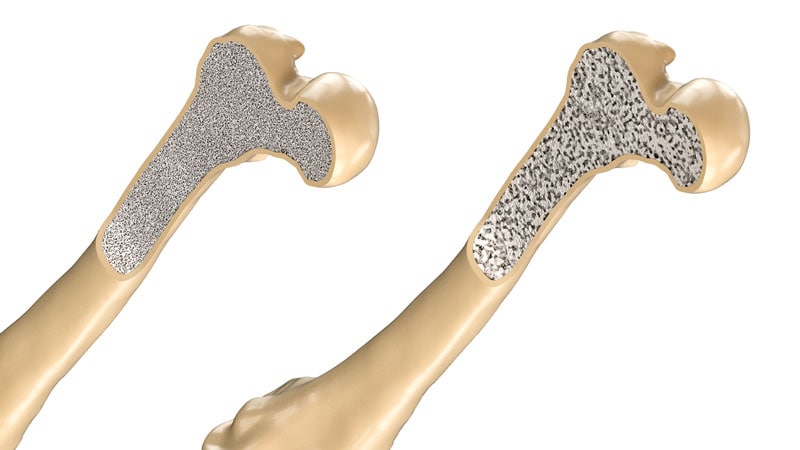

Osteoporosis

ASBMR 2023Bariatric Surgery Linked to Fracture Risk -

ASBMR 2023Higher Fracture Risk Not Seen With SGLT2 Inhibitors -

ASBMR 2023Premenopausal Osteoporosis: What to Do After Denosumab -

ASBMR 2023Fractures Beget Fractures at Any Age